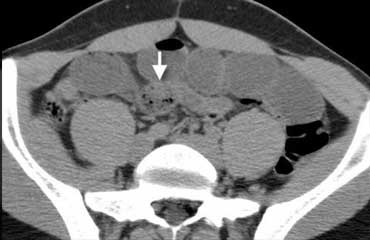

Khí trong ổ phúc mạc ở bệnh nhân nghi ngờ viêm ruột thừa. Khí được nhìn thấy rõ hơn trên hình ảnh với cửa sổ phổi ở bên phải.

Sự hiện diện của khí tự do trong ổ phúc mạc là bằng chứng của thủng tạng rỗng, và là chỉ định cấp cứu ngoại khoa.

Luôn khảo sát hình ảnh ở cửa sổ phổi để phát hiện khí tự do trong ổ bụng tốt hơn (hình minh họa).